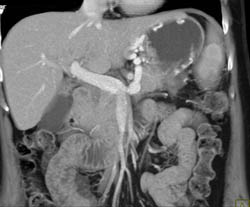

Bulky Gastric Cancer With Nodes